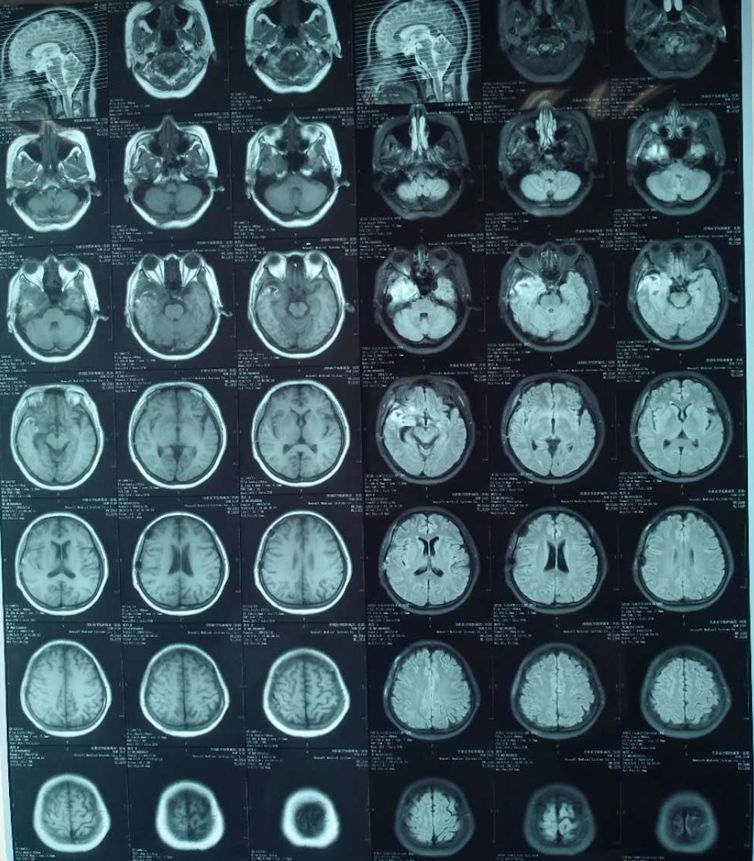

术后复查头CT,颅内未见出血,中线居中,环池清楚。

术后复查的核磁,右侧海绵窦内海绵状血管瘤全部切除,未见残留征象。

术后病理示:海绵状血管瘤